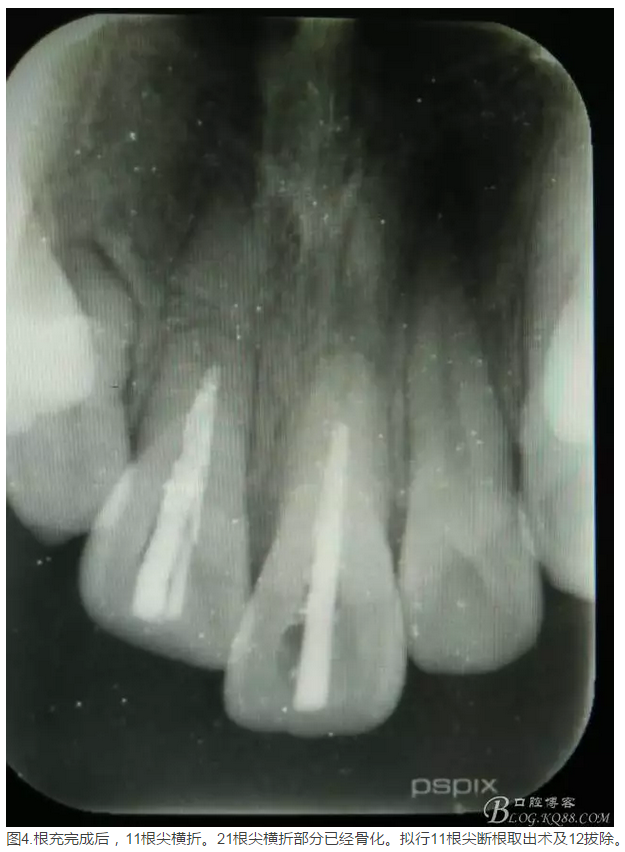

患者、李xx、男、15歲,主訴:牙不齊,矯正牙齒。專科檢查:發(fā)現(xiàn)11、21根尖三分之一折斷,患者否認(rèn)有外傷史。正畸科治療建議如圖1.。術(shù)前簽手術(shù)同意書。